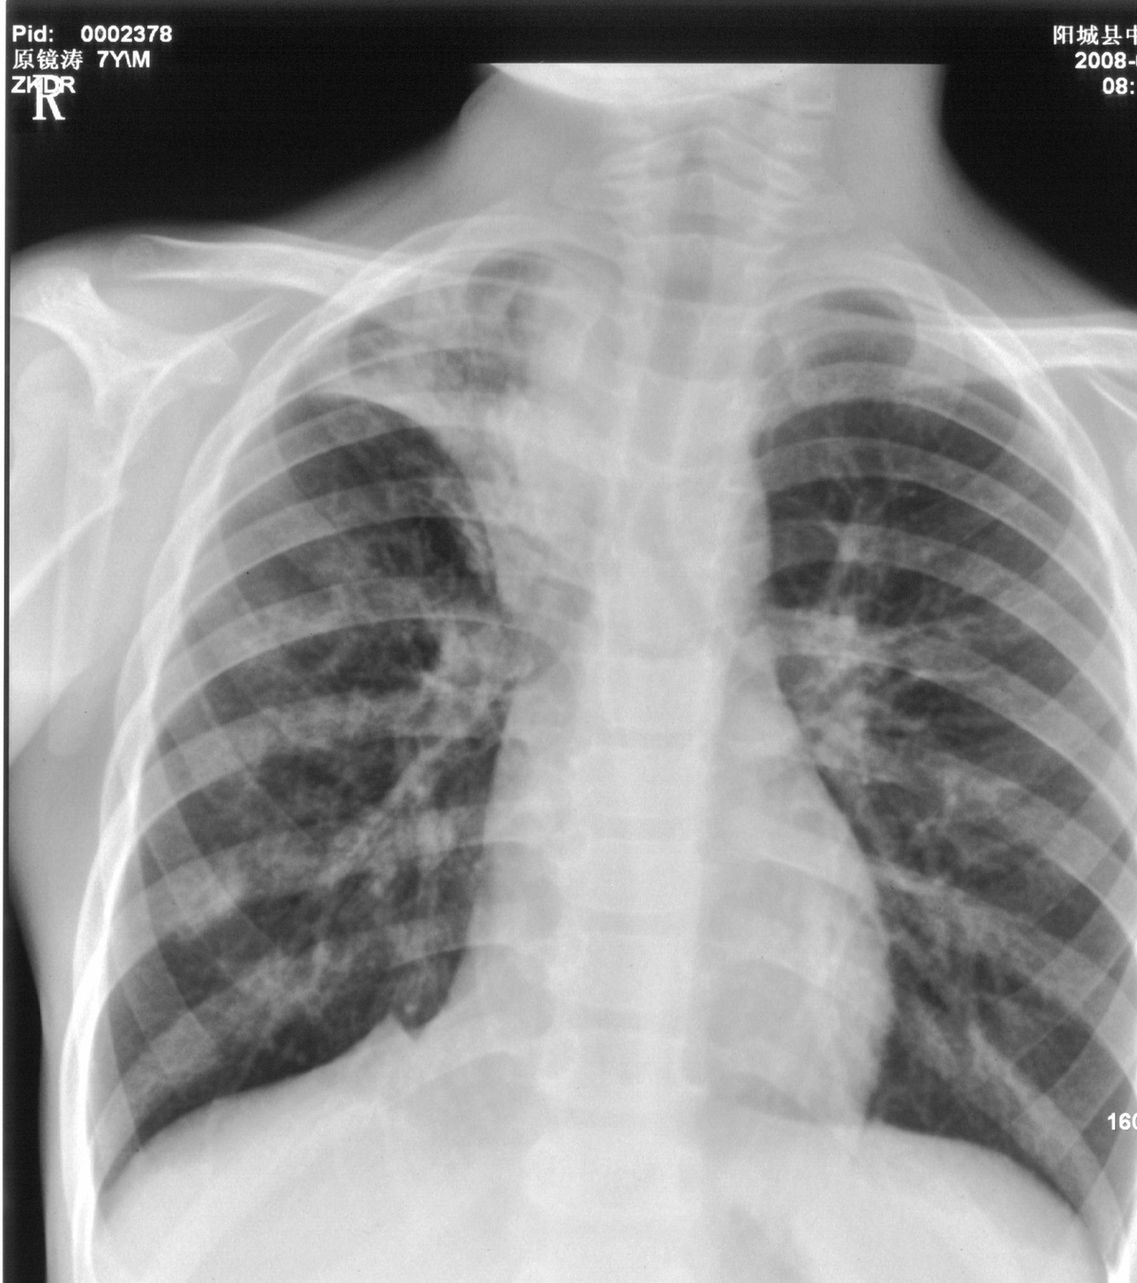

9月8号平片检查情况:

右上肺不均匀密度增高,体积变小,水平裂弧状上移,纵隔内有肿大的淋巴结。考虑:

1、右上肺炎(吸收期),纵隔淋巴结肿大压迫右上叶肺膨张不全

2、纵隔淋巴结结核不能排除

建议继续抗炎治疗短期复查